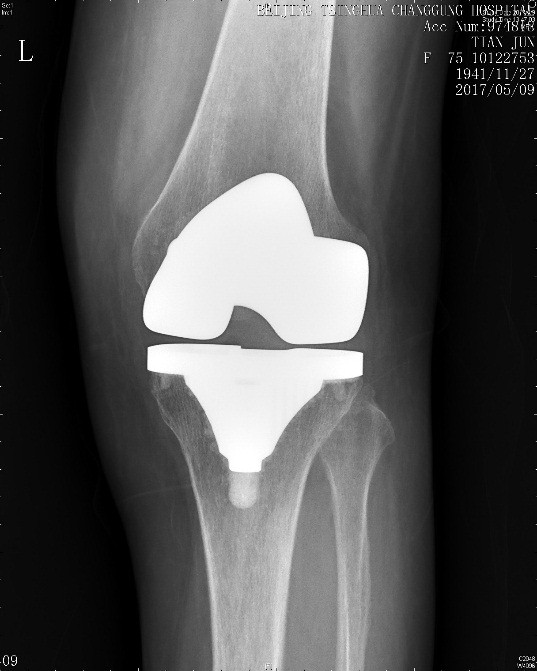

田阿姨今年75岁,左膝关节肿胀,疼痛,活动受限有5年多了,因为膝关节的问题去过许多大医院,专家都建议她做膝关节置换手术治疗,今年终于下定决心,在某专科医院做了左膝关节置换手术。手术做完2个月,田阿姨的膝关节仍然疼痛明显,下不了地,家属推轮椅来到了医院就诊。仔细查体可见左膝关节前可见手术伤口,愈合良好,无红肿渗出。左膝关节肿胀,伤口周围压痛明显,左膝关节屈伸活动明显受限,屈伸活动时伴疼痛,膝关节活动度为10-80度,左下肢髂腰肌肌力减弱。

图1 膝关节置换术后左膝关节X线检查